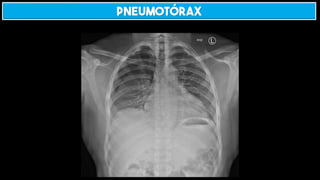

HEMOTÓRAX E PNEUMOTÓRAX

Pneumotórax